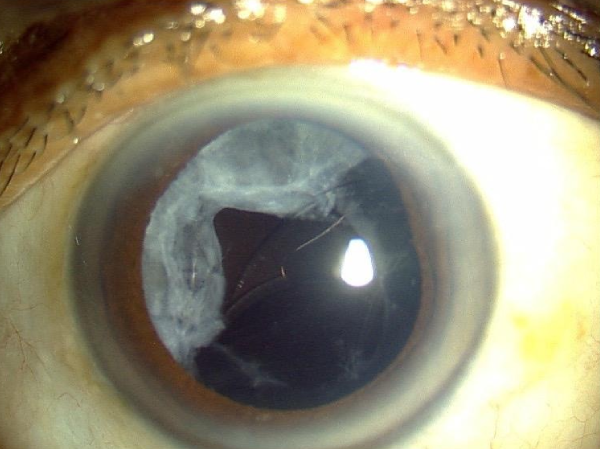

Difficult Cataract Surgeries : Posterior Polar Cataract

Posterior polar cataract pre operative eye condition in Trivandrum

Pre-Operative